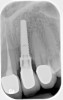

Fig 3. Fractured abutment screw.

Figure 3

Screw loosening and fracture (Figure 3 and Figure 4) have been consistent problems in implant dentistry.6 Several adaptations have been made to the screw and implant design to minimize these issues, such as the transition from an external to internal connection and changing both the screw composition and coating. Implant manufacturers offer various implant connection and screw designs, and these designs are modified as newer and enhanced materials become available.